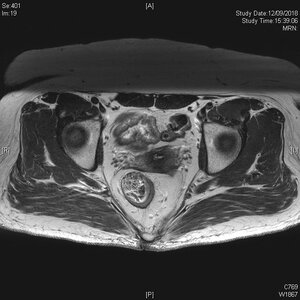

為減低局部復發的風險,腫瘤切除必須包涵足夠的組織邊緣。高於病灶的組織邊緣相對容易處理,但遠端(即近肛門位置)及環周的組織邊緣,必需要在術前經臨床、內視鏡及放射影像謹慎評估。於上述三個範疇中,盆腔磁力共振影像掃描為最重要的一項,因它能客觀地推算全直腸系膜切除術可切除的遠端及環周的組織邊緣範圍,亦能顯示直腸腫瘤與鄰近器官之間的關係、有否出現可疑淋巴結(有機會藏有惡性細胞)、以及有否出現壁外靜脈入侵。

直腸腫瘤入侵鄰近的子宮

直腸系膜內的淋巴結直迫系膜筋膜 – 需考慮術前新輔助治療